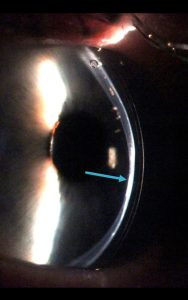

قوز قرنیه

کراس لینک